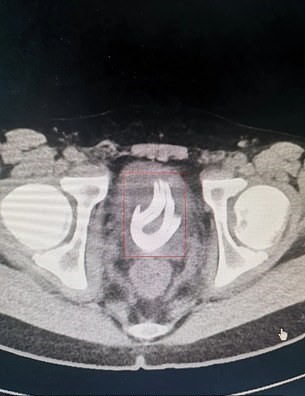

Doctors were shocked to discover the tangled cord inside the boy’s bladder on an X-ray scan.

Medics immediately scheduled Xiao He to undergo the surgery and they pulled out the 2ft. long electrical wire from his urethra.